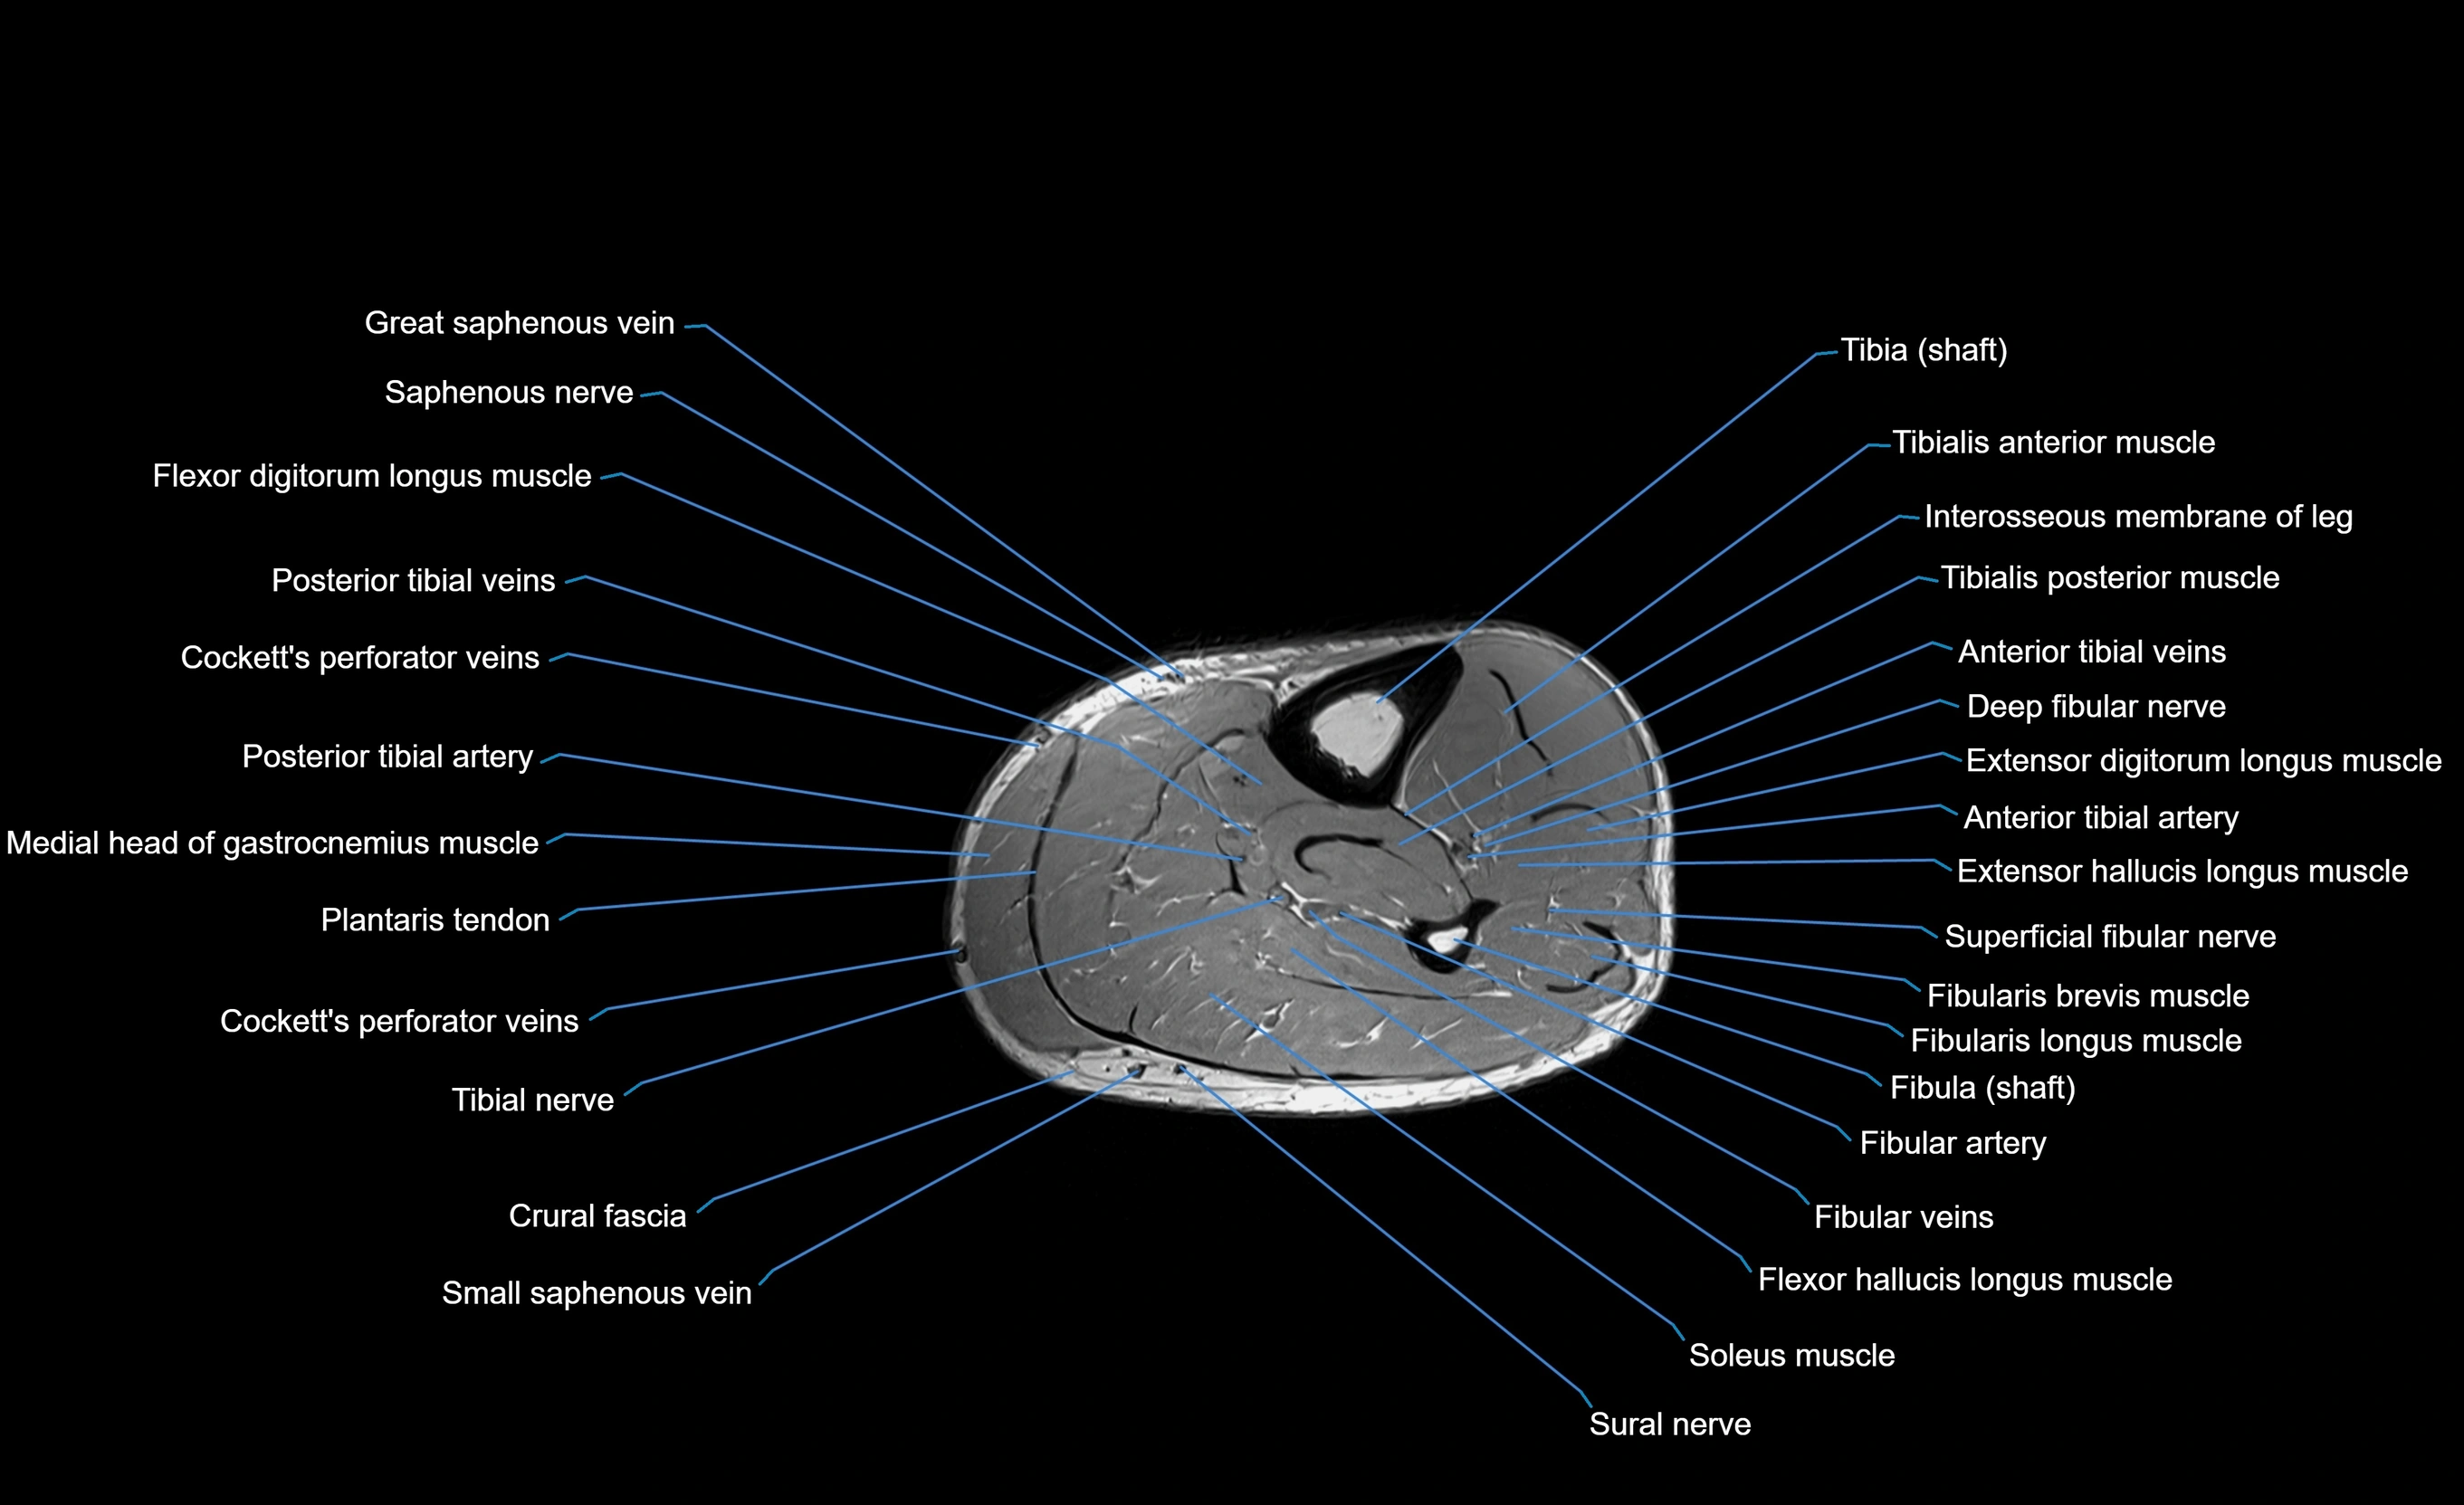

MRI image